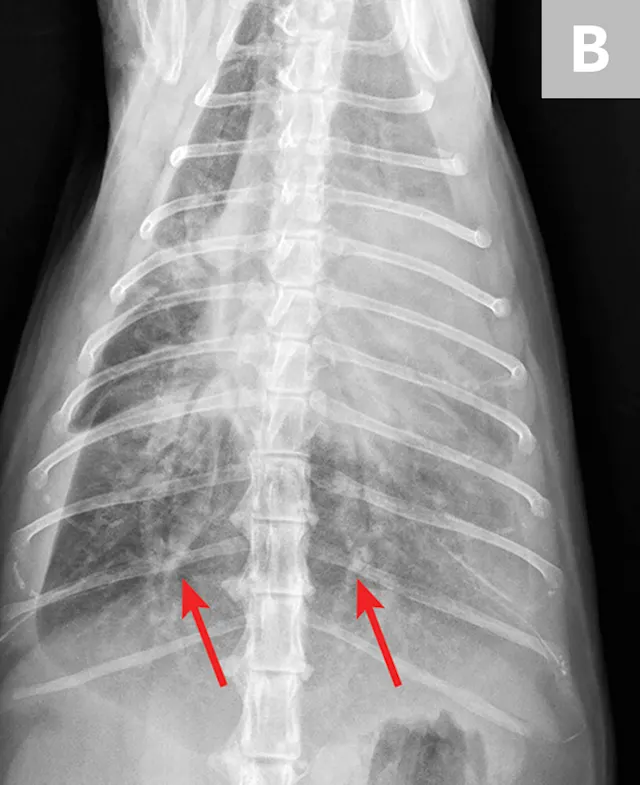

Overt cardiomegaly may be understated on radiographs because of changes in internal diameter that do not affect the overall cardiac silhouette. Vertebral heart score >9.3 supports a CHF diagnosis.1 Pulmonary venous congestion can be absent, and pulmonary arterial distension may be appreciated. The presence of pleural effusion with simultaneous pulmonary infiltrates is supportive of CHF (Figure 1).2

Congestive heart failure. Note the pleural effusion (arrows).